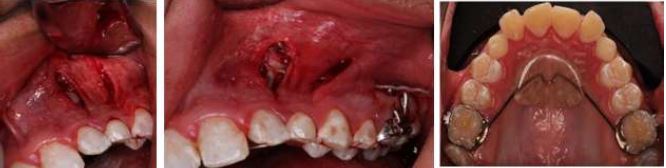

Clinical Procedure

Initially, the patient and her mother received detailed information about the procedure, who accepted and authorized the treatment plan by signing the informed consent. The surgical intervention, performed under local anesthesia, began with a vertical incision with a 15c scalpel blade distal to the area of tooth 23 that involved the free gingiva up to the mucogingival line, without compromising the attached gingiva or the lining mucosa. The soft tissue was then detached and a syndesmotomy and osteotomy exposed the dental crown (Figure 3). Afterwards, a buccal button was cemented, followed by conductive osteotomy that included a decortication distal to 23. In this way, a channel or traction path of the tooth allowed greater movement of the impacted tooth.

Subsequently, the procedure created a subperiosteal tunnel from 23 to 26 and soft tissue was dissected with TKN1 and TKN2® 1 tunneling instruments and Allen® KPA scalpel. A 1.5 x 12 mm SIN® infrazygomatic miniscrew placed in the area of 26 and 27 looked to provide anchorage and direct movement by applying forces of 60 grams. A measurement of force with an Eisco Labs® dynamometer was useful to monitor the distalization of the impacted tooth and place it in the ideal area for eruption. Next, a 3-mm vertical incision was made in the area of 26, and a second-generation elastic chain was passed through the subperiosteal tunnel from the button on 23 to the mini-implant (Figure 3). Finally, after obtaining hemostasis, simple stitches with Vicryl® 5.0 were placed.

VISTA Technique Surgical Procedure, Case 1

FIGURE 3

VISTA technique, incisions, position of the direct cementing button, second-generation chain through the subperiosteal tunnel, and miniscrew in the infrazygomatic area. Source: the authors with permission from the patient.

After receiving authorization of the treatment plan from the patient's parents and signed informed consent, a modified palatal button with double tubes welded to the upper first molar bands was installed. In addition, a steel arm welded to the 26 band was included in order to replace the miniscrew of the technique described by Chang (Figure 8).

The surgical intervention was performed under local anesthesia. It began with two vertical incisions, the first in the buccal gingiva between 22 and 63, and the second in the buccal gingiva at the level of 24 to make the subperiosteal tunnel by dissecting the soft tissue. An osteotomy was performed to discover the crown of 23 and a conductive osteotomy towards the distal. The button was adhered to the crown of 23 and an elastic chain was installed from the buccal button of 23 through the subperiosteal tunnel to the post welded to the band of 26. Thus, distalization force of 23 could be applied, and improve its eruption pathway (Figure 8).

On the other hand, tooth 13 underwent a closed surgical window that began with an incision at the height of the crown. An osteotomy was performed in its cervicoincisial length, adhesion of the button to the crown, and installation of an elastic chain. A 0.017" x 0.025" TMA cantilever was adapted to the auxiliary band tube of tooth 16, to which a chain previously installed in the button of 13 was adapted, initially with a distalization vector force. Both approaches were completed with hemostasis and suture.

Surgical Procedure with VISTA Technique, Case 2

FIGURE 8

Surgical procedure showing VISTA technique, incisions, position of the button with direct cementation, second generation chain, through the subperiosteal tunnel, and the modified tooth-supported palatal button, cemented through bands to teeth 16 and 26. Source: the authors with permission from the patient.